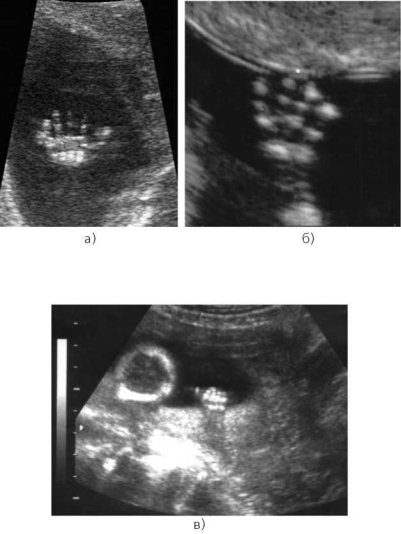

Пороки плода на узи

Пороки плода на узи 119 фотографий